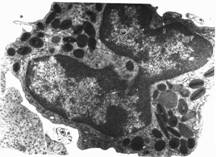

Monocitul

Este leucocitul cel mai mare din sange, 16-20 de microni, are forma sferica sau ovalara, cu citoplasma abundenta, slab bazofila, putand prezenta granulatii nespecifice, azurofile. Nucleul este mare, deseori reniform, sarac in cromatina, avand aspect spongios. Cromatina este dispusa sub forma unor retele fine , slab cromatica, nu contine nucleol. Este socotit histiocit sanguin.

Numarul lor este de 6-10 la 100 leucocite. Cresterea numarului lor poarta denumirea de monocitoza, apare in boli infectioase : sifilis, etc.

Fig. 9

Fig. 10 Monocit, col MGG, ob.X40